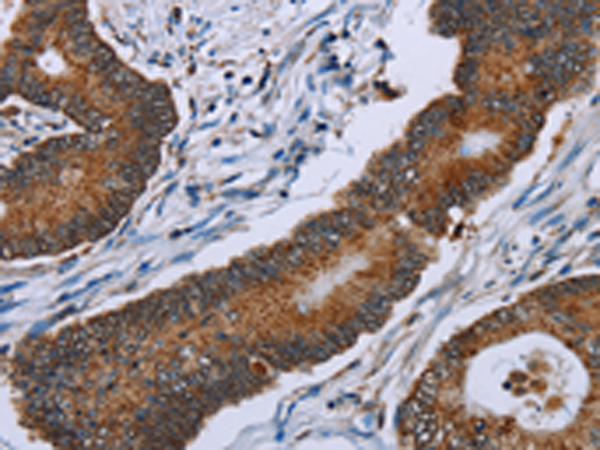

分类: 科研抗体货号: P08443别名:应用: IHC反应种属: Human, Mouse, Rat